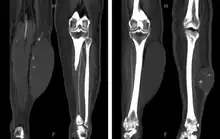

CT showing lower extremity hematomas[9][10]